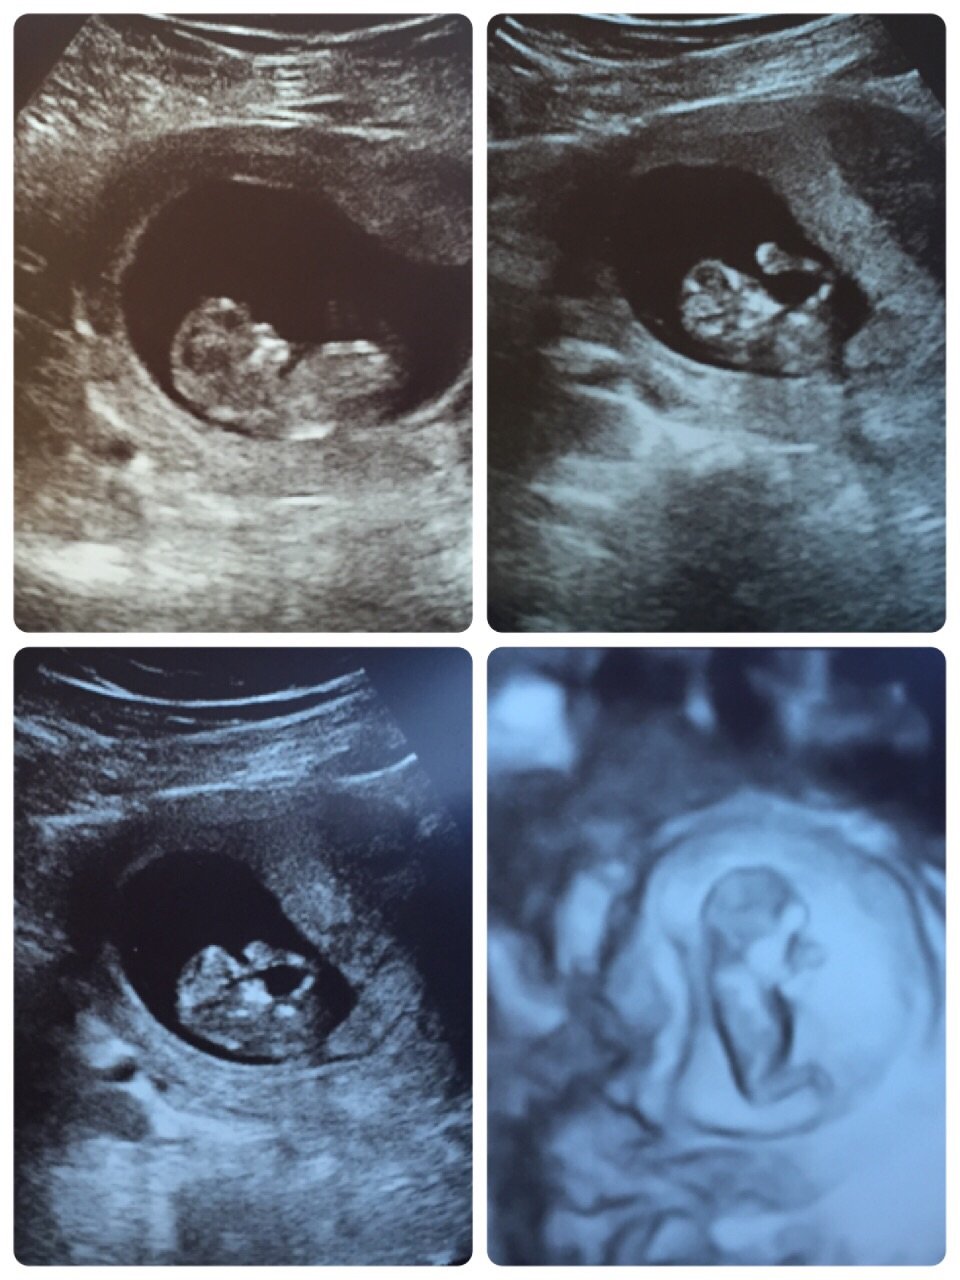

Look at my 11 weeks 1 day ultrasound

so cool thought I'd share

The baby moving